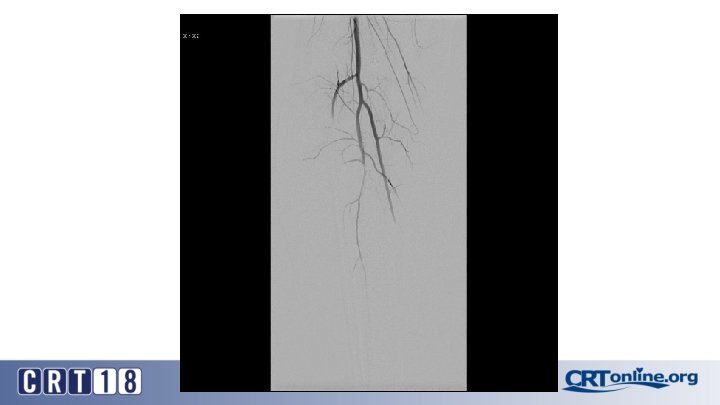

Blue Toe Syndrome

Returns Next day

Failed recanalization: BKA